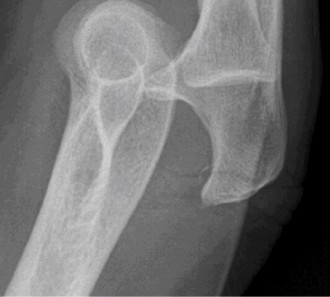

Anteroposterior (AP) and lateral radiographs of the right elbow were obtained.

Initial AP and Lateral Radiographs:

These views clearly demonstrated a posterior dislocation of the ulnohumeral joint. The olecranon was positioned posterior to the distal humerus. Crucially, the radiographs revealed associated fractures.

- There was a comminuted fracture of the radial head (Mason Type III).

- A significant coronoid process fracture was identified, involving approximately 50% of the coronoid height, consistent with a Regan-Morrey Type II fracture.

- Evidence of avulsion fractures from the medial epicondyle (consistent with MCL injury) and lateral epicondyle (consistent with LCL complex injury) were also noted, indicating extensive soft tissue disruption.

(Representative initial AP radiograph illustrating the elbow dislocation and comminuted radial head fracture.)

Given these findings, a diagnosis of a terrible triad injury of the elbow was made.